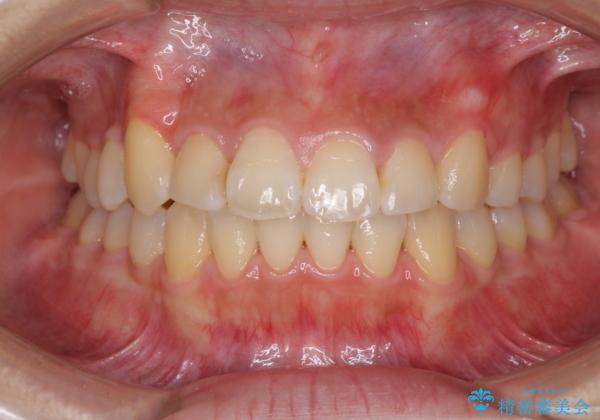

- 前歯のでこぼこと乳歯が残るほどの八重歯を気にして来院された患者様です。

非抜歯にてワイヤー矯正にて治療することとしました。(ただし、親知らずと乳歯は抜歯)

犬歯は歯根が太く長いため、移動には時間を要します。しかし、犬歯は機能面から考えて残すことを選択したいため、長期間をかけて治療を行うこととしました。

治療の度に歯列が改善していったため、長期間の治療も楽しく過ごしていいただき、満足のいく仕上がりとなりました。